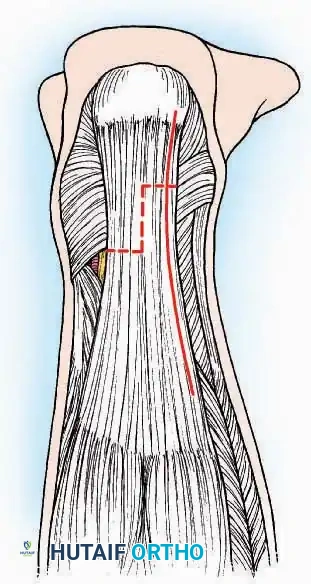

Dorsomedial Approach

Surgical Technique:

* Incision: Begin just proximal to the IP joint and extend proximally for 5 cm, running parallel and strictly medial to the EHL tendon.

* Exposure: Divide the superficial fascia. Identify and retract the EHL tendon laterally.

* Capsulotomy: The capsule can be incised longitudinally in the exact plane of the skin incision, allowing for subperiosteal elevation of the capsule medially and laterally, preserving the vascular supply to the medial skin flap.